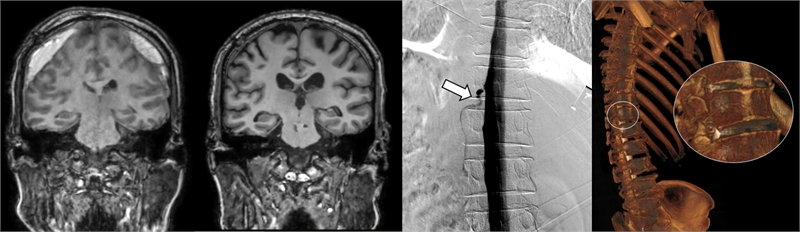

▲ (왼쪽) DSM으로 확인한 누공 위치, (오른쪽) 측위 CT 척수 조영술로 확인한 뇌척수액 정맥 누공 3D 영상

세브란스병원은 최근 DSM을 국내 최초로 도입해 이와 같은 기존 진단법의 한계를 극복했다. DSM(Digital Subtraction Myelography, 디지털 감산 척수조영술)은 척수에 조영제를 주입하고 모니터 화면으로 뇌척수액의 흐름을 실시간으로 확인할 수 있다. 이를 통해 뇌척수액이 새나가는 구멍을 정확하게 찾아낼 수 있게 됐다.

DSM과 더불어 세브란스병원이 함께 진행 중인 측위 CT 척수 조영술까지, 모두 뇌척수액 정맥 누공을 진단할 수 있는 최신 기법이다.